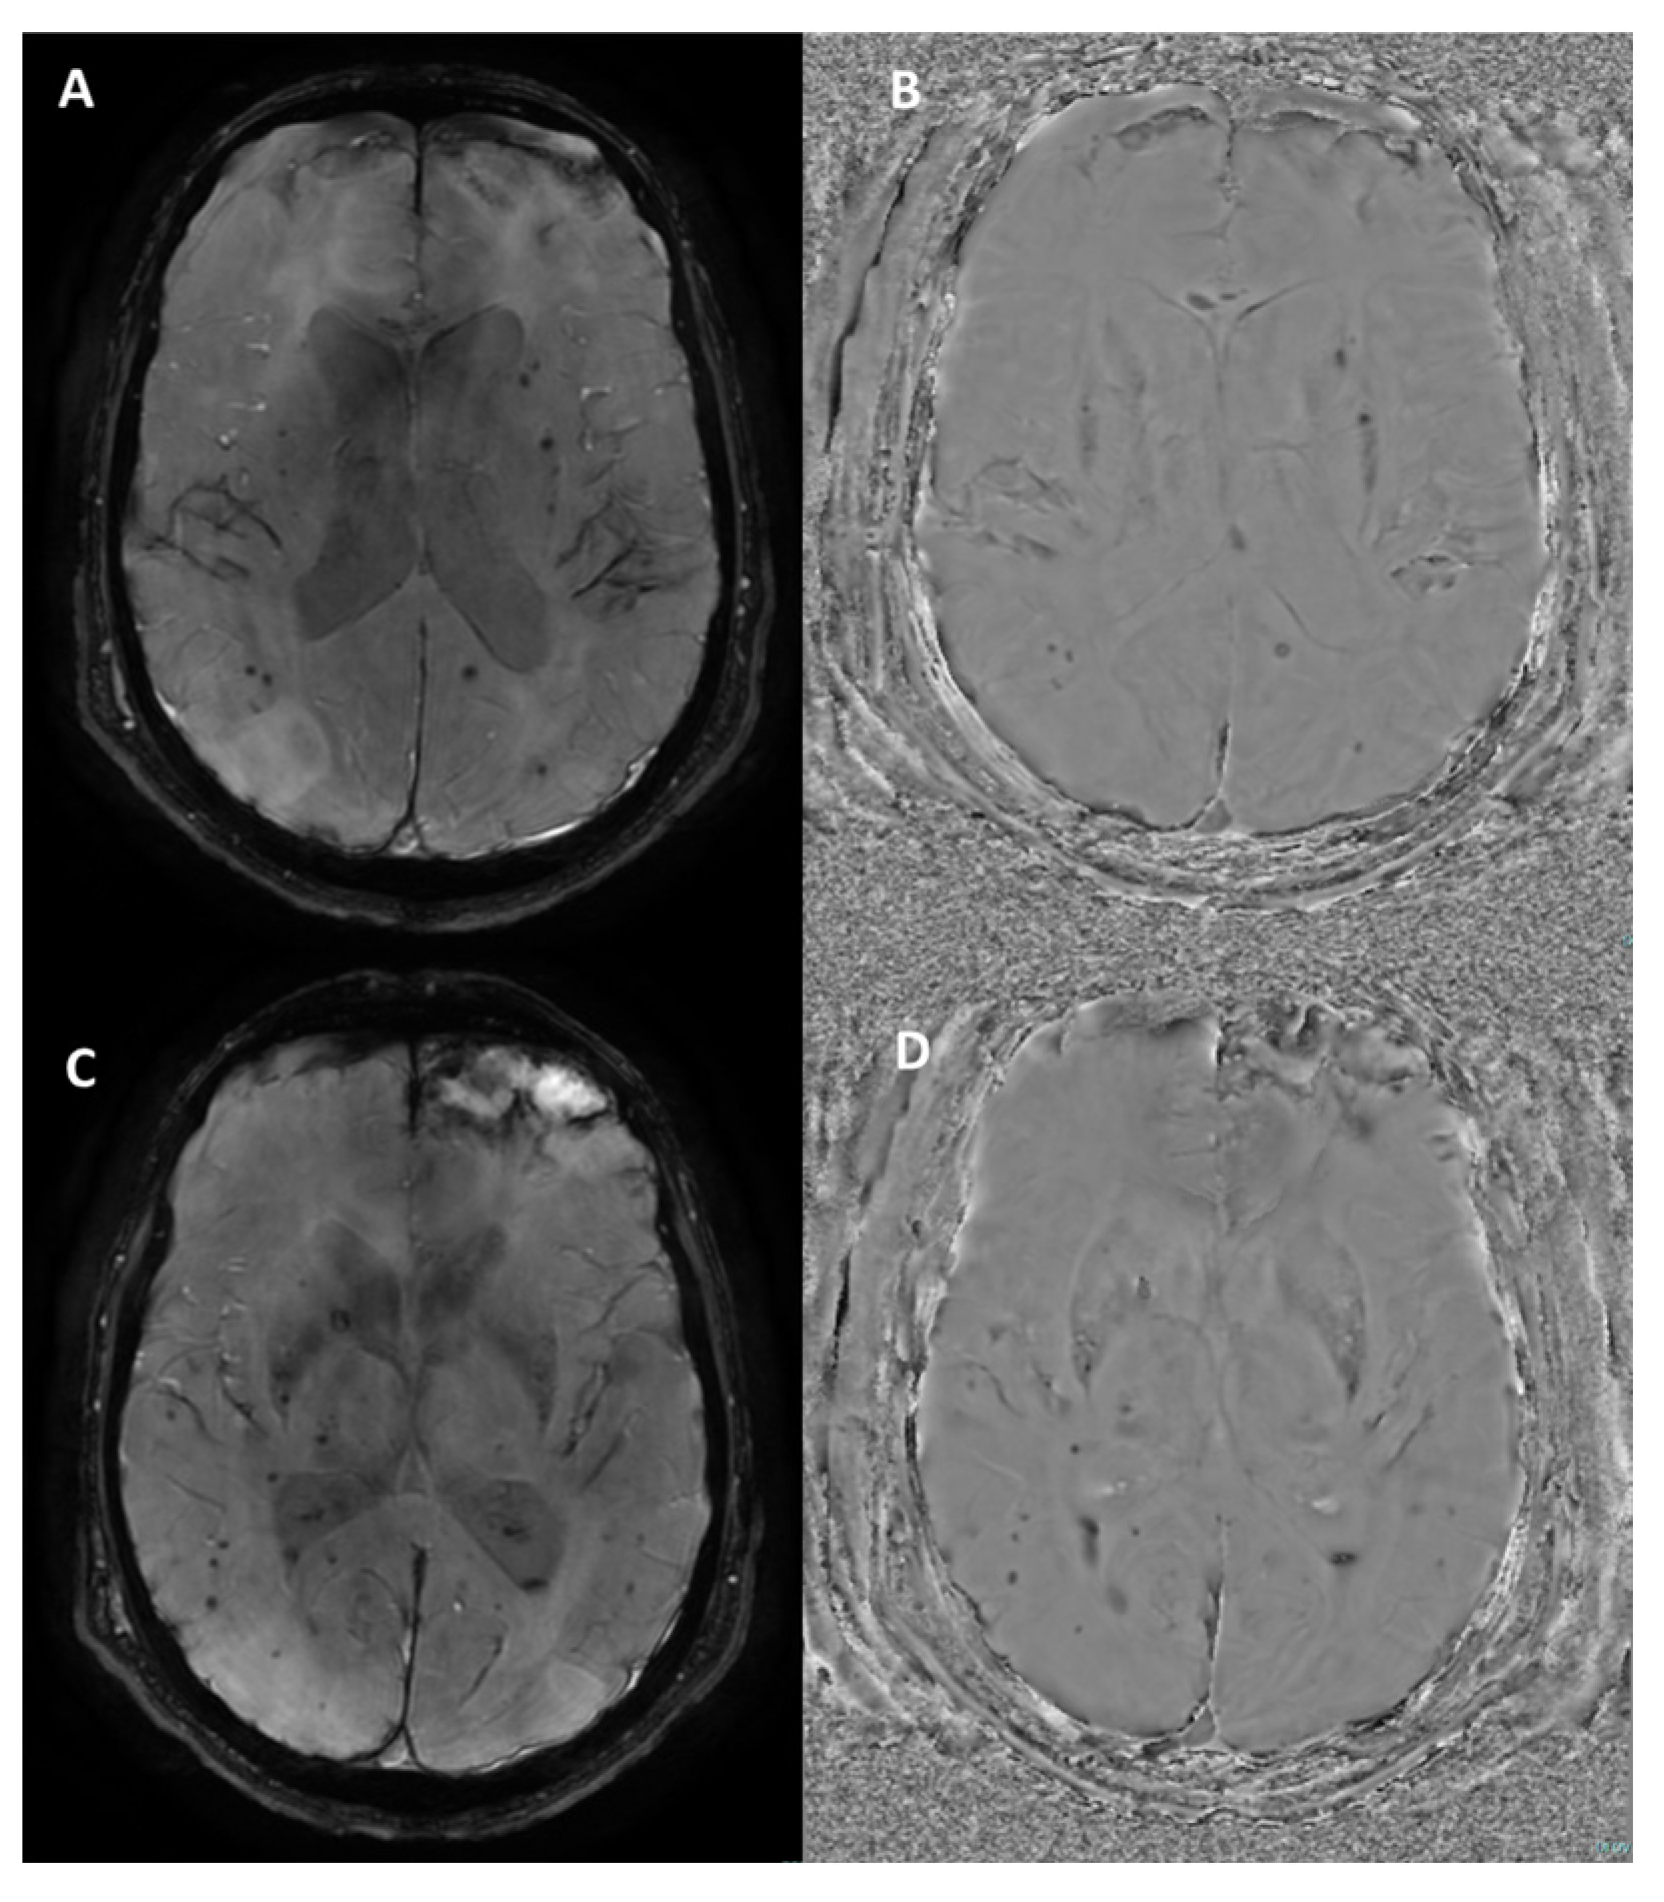

4.2. Multiple Sclerosis

- Mesker, D.J.; Poels, M.M.F.; Ikram, M.A.; Vernooij, M.W.; Hofman, A.; Vrooman, H.A.; van der Lugt, A.; Breteler, M.M.B. Lobar Distribution of Cerebral Microbleeds. Arch. Neurol. 2011, 68, 656–659. [Google Scholar] [CrossRef] [PubMed]

- Rubin, A.; Waszczuk, Ł.; Trybek, G.; Kapetanakis, S.; Bladowska, J. Application of susceptibility weighted imaging (SWI) in diagnostic imaging of brain pathologies—A practical approach. Clin. Neurol. Neurosurg. 2022, 221, 107368. [Google Scholar] [CrossRef]

- Sharma, R.; Dearaugo, S.; Infeld, B.; O’Sullivan, R.; Gerraty, R.P. Cerebral amyloid angiopathy: Review of clinico-radiological features and mimics. J. Med. Imaging Radiat. Oncol. 2018, 62, 451–463. [Google Scholar] [CrossRef] [PubMed]

- Linn, J.; Halpin, A.; Demaerel, P.; Ruhland, J.; Giese, A.; Dichgans, M.; van Buchem, M.; Bruckmann, H.; Greenberg, S. Prevalence of superficial siderosis in patients with cerebral amyloid angiopathy. Neurology 2010, 74, 1346–1350. [Google Scholar] [CrossRef] [PubMed]

- Lopes, P.A.; Raposo, N.; Charidimou, A.; Zotin, M.Z.; Gurol, M.E.; Greenberg, S.; Viswanathan, A. SWI versus GRE-T2*: Assessing cortical superficial siderosis in advanced cerebral amyloid angiopathy. Rev. Neurol. 2024, 180, 532–538. [Google Scholar] [CrossRef]

- Charidimou, A.; Boulouis, G.; Frosch, M.P.; Baron, J.-C.; Pasi, M.; Albucher, J.F.; Banerjee, G.; Barbato, C.; Bonneville, F.; Brandner, S.; et al. The Boston criteria version 2.0 for cerebral amyloid angiopathy: A multicentre, retrospective, MRI–neuropathology diagnostic accuracy study. Lancet Neurol. 2022, 21, 714–725. [Google Scholar] [CrossRef]